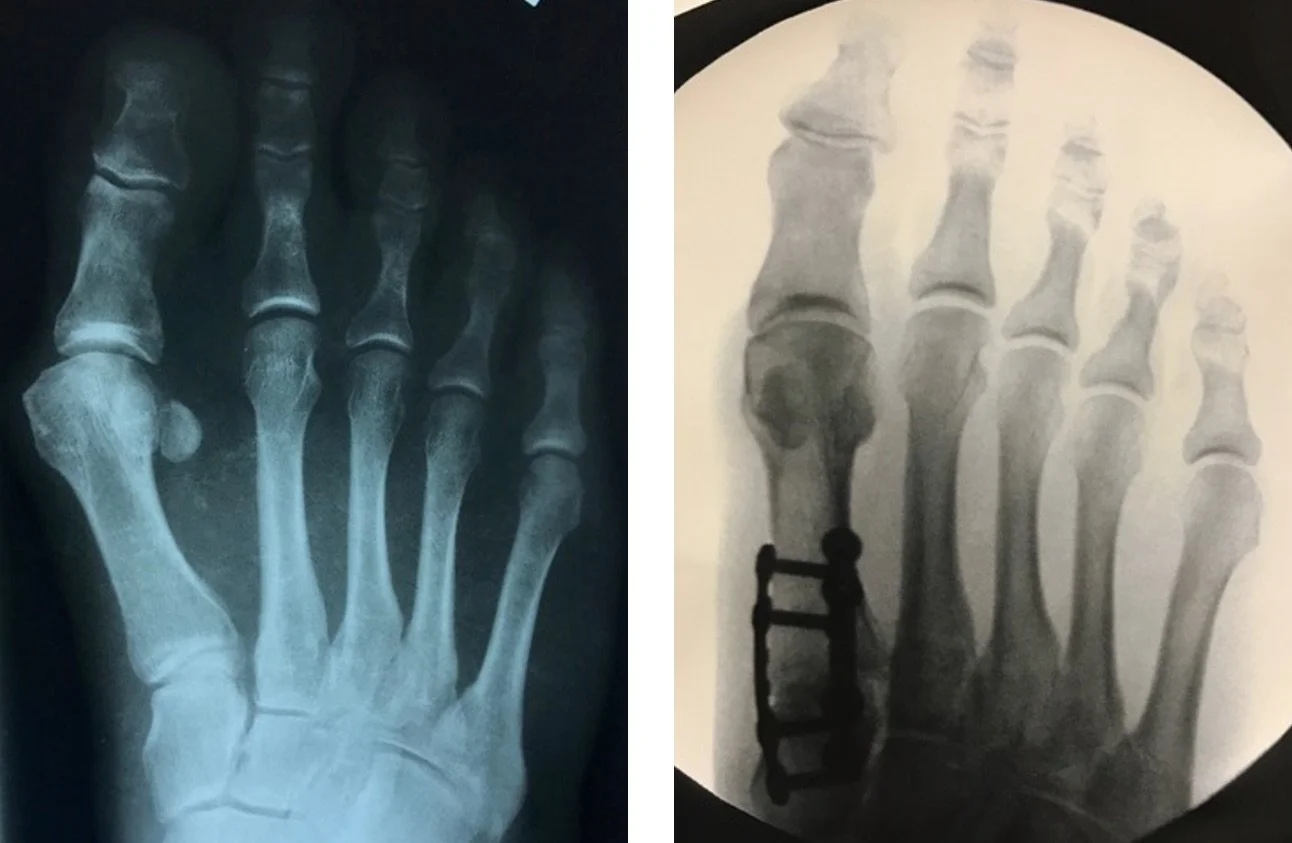

A bunionectomy refers to surgical correction of a bunion (hallux valgus), a deformity in which the big toe drifts toward the smaller toes, creating a painful prominence along the inside of the foot. Surgery is considered when pain persists despite non-surgical treatment.

Multiple surgical techniques may be used depending on deformity severity, anatomy, and patient goals, including minimally invasive osteotomy, traditional metatarsal osteotomy, or Lapiplasty.

Metatarsal osteotomy with fixation to correct angular deformity

Lapiplasty, which corrects the deformity at its source by stabilizing the first tarsometatarsal joint